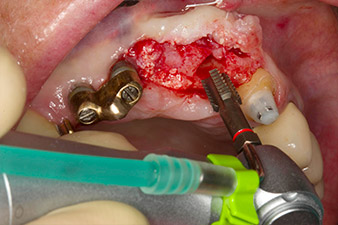

Después de la cicatrización primaria, los tejidos blandos se modelaron con ayuda del puente con base reconstruida. Dos meses después, se procedió a la exposición del área con una incisión de la cresta maxilar en sentido ligeramente palatino (figura 2).

El hueso alveolar de la posición 22 resultó tener unas dimensiones suficientes. Las figuras 2 y 4 muestran la preparación del lecho del implante, el corte de rosca y la colocación del implante con el equipo Implantmed.

Para compensar la pérdida de hueso periodontal y conseguir un resultado estético, el implante se combinó con una regeneración ósea guiada con material sustituto xenógeno y con una membrana de colágeno

(figuras 5 y 6).